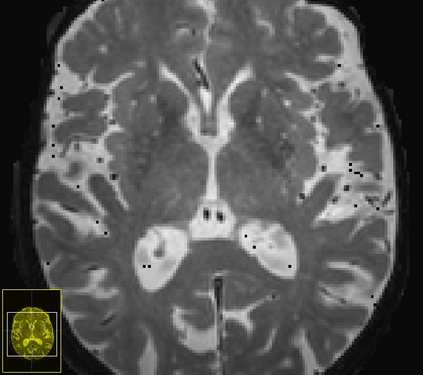

Imaging markers of cerebral small vessel disease provide valuable information on brain health, but their manual assessment is time-consuming and hampered by substantial intra- and interrater variability. Automated rating may benefit biomedical research, as well as clinical assessment, but diagnostic reliability of existing algorithms is unknown. Here, we present the results of the \textit{VAscular Lesions DetectiOn and Segmentation} (\textit{Where is VALDO?}) challenge that was run as a satellite event at the international conference on Medical Image Computing and Computer Aided Intervention (MICCAI) 2021. This challenge aimed to promote the development of methods for automated detection and segmentation of small and sparse imaging markers of cerebral small vessel disease, namely enlarged perivascular spaces (EPVS) (Task 1), cerebral microbleeds (Task 2) and lacunes of presumed vascular origin (Task 3) while leveraging weak and noisy labels. Overall, 12 teams participated in the challenge proposing solutions for one or more tasks (4 for Task 1 - EPVS, 9 for Task 2 - Microbleeds and 6 for Task 3 - Lacunes). Multi-cohort data was used in both training and evaluation. Results showed a large variability in performance both across teams and across tasks, with promising results notably for Task 1 - EPVS and Task 2 - Microbleeds and not practically useful results yet for Task 3 - Lacunes. It also highlighted the performance inconsistency across cases that may deter use at an individual level, while still proving useful at a population level.